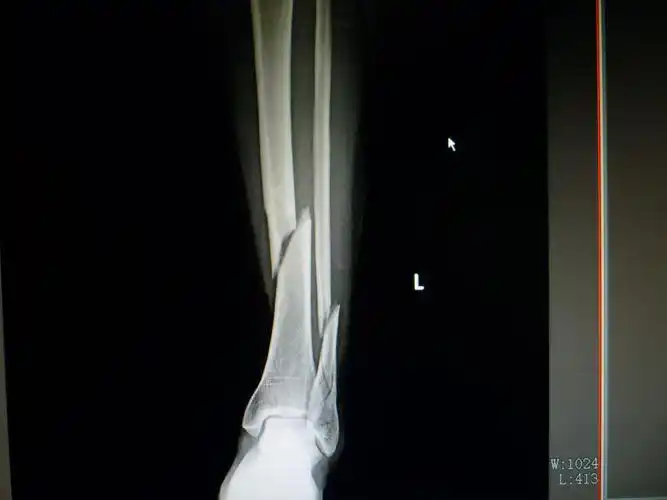

三例胫腓骨远端骨折

兔年本历年说我四肢容易受伤害,六月中刚受伤,七月初脚趾头又给磕坏了